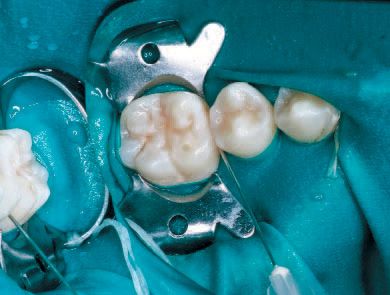

Remove the Proximal-Tip and rinse the area with a water/air spray for 30 seconds, then finish with air drying only for an additional 10 seconds. Apply ICON-Dry (99% ethanol) to the treated area with the metal micro tip and let it sit for 30 seconds, then air dry (Fig. 7). Fasten a new Proximal-Tip foil matrix to the end of the ICON-Infiltrant syringe and slide it interproximally, again with the green side toward the lesion. Turn the handle 1½ to 2 turns to allow an ample amount of the resin to flow into the site (Fig. 8). Wait three minutes, then remove the foil matrix and any excess resin with dental floss. Cure the area from both the buccal and lingual aspects with a visible light source for 40 seconds (Fig. 9).

Fasten a new Proximal-Tip foil matrix to the end of the

ICON -Infiltrant syringe and slide it interproximally,

again with the green side toward the lesion.

Turn the handle 1 ½ to 2 turns to allow an ample

amount of the resin to flow into the site (Fig. 8).

After removing the matrix,

cure the area from both the buccal and

lingual aspects with a visible light source

for 40 seconds (Fig. 9)

Screw a new Proximal-Tip onto the ICON-Infiltrant syringe and repeat the procedure, again being sure to leave the resin in contact with the lesion for an additional 1 minute as research has shown this dual application is critical to the success of an adequate protective resin barrier.17